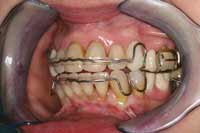

Figure 12 Upper-arch clean up, orthopedic expansion, and orthodontics completed.

Figure 13 Note the rectangular wire used to create ideal torque.

Figure 14 Lower-arch clean up, orthopedic expansion, and orthodontics completed.

The orthopedic position established in Phase 1 was maintained in Phase 2 by constructing anterior composite incisal ramps/blocks for the lower anterior incisor occlusion. In the posterior, occlusal blocks were built on the occlusal surface of the second molars. This tripod (Figure 10) maintained the jaw and bite trajectory, which was established in Phase 1 through the NDA and the nighttime deprogrammer with palatal ramp. With this functional tripod established, the Phase 2 goals of orthopedic expansion could be accomplished as well as the orthodontic goals of rotating, leveling, and alignment. The upper-arch orthopedic development was accomplished through a fixed Hyrax expansion appliance (Figure 11 and Figure 12). The lower arch development was accomplished along with the upper arch and through use of straight wire techniques (Figure 13 and Figure 14). Final coupling of the dentition was accomplished through verticalization with eruption of the teeth through elastics. Phase 2 took 13 months. The patient then was placed in retention for an additional 6 months (Figure 15).